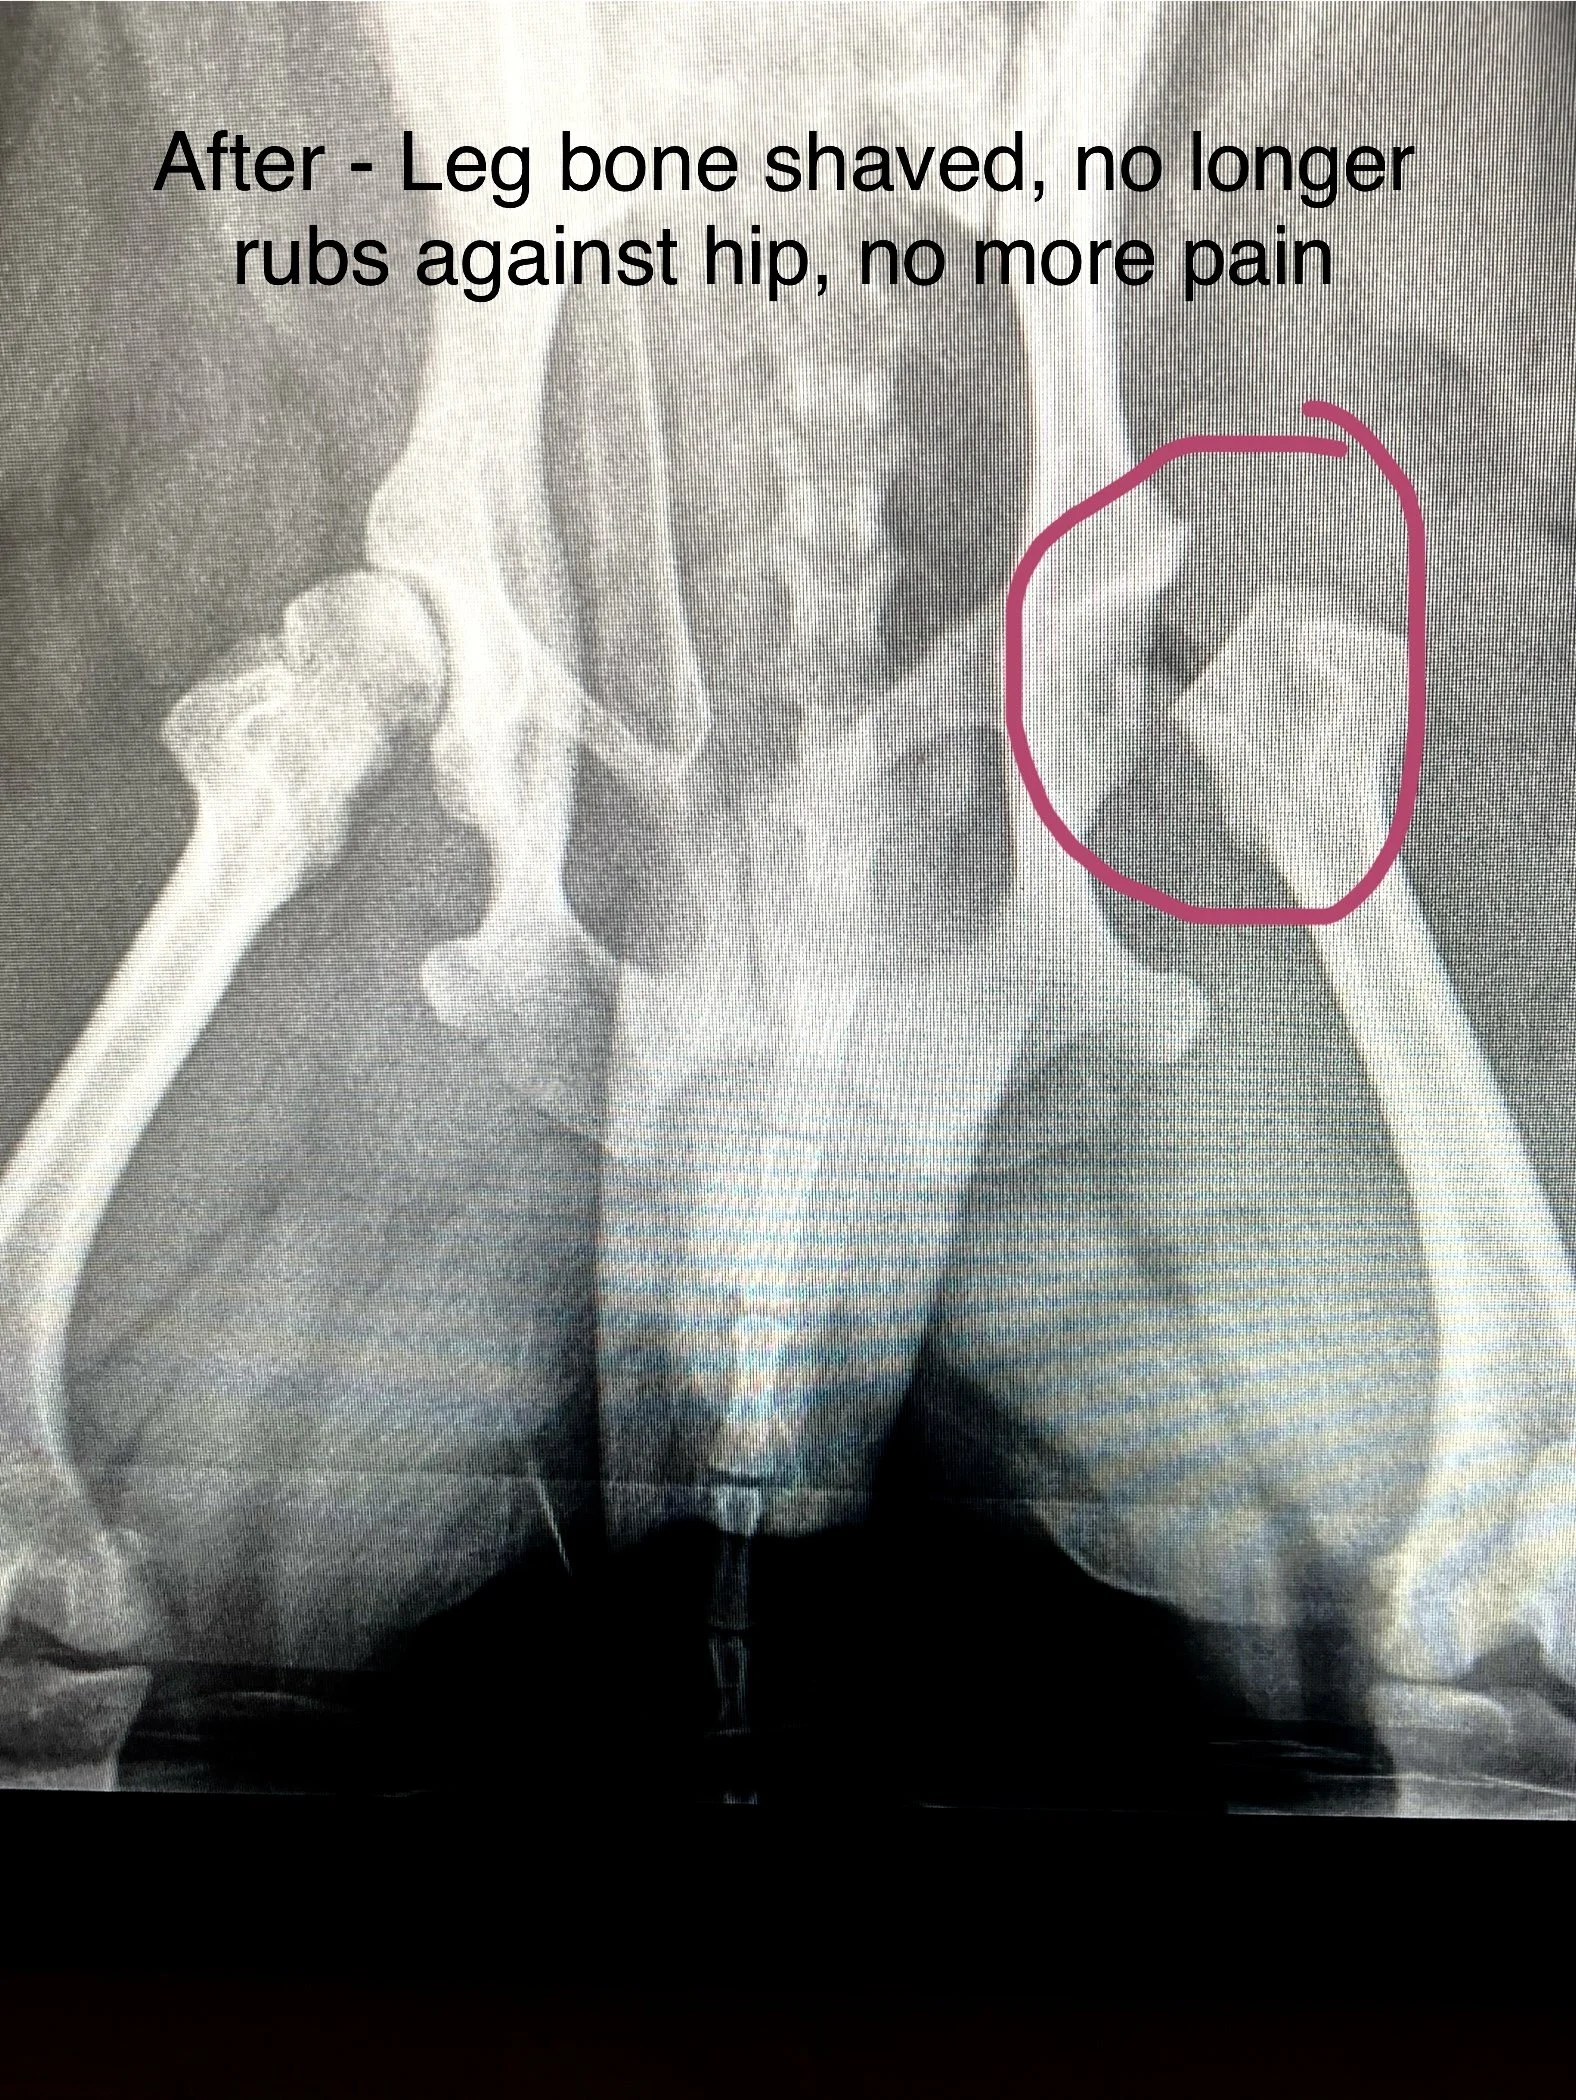

Despite his amazing life and band, something was troubling Ziggy. After his concerts, he felt more and more sore. His hips would hurt after each recording session. He went to see Dr. Doodle, who ran a number of tests. She discovered that Ziggy was born with a condition called hip dysplasia, where the ball and socket of the hip don’t fit together properly. Instead of sliding smoothly, they rub and grind, leading to gradual deterioration and significant chronic pain.

After arriving on Earth, Ziggy heads straight to New Orleans, where he is treated by his incredible medical team. They take his x-ray and administer the anesthesia. While Ziggy is peacefully dreaming, they make the incision and remove the section of bone that is causing his dysplasia.

It was a successful surgery! His doctor prescribes lots of rest and relaxation, and his healing begins. After 6 weeks of rest, he will finally be pain free!